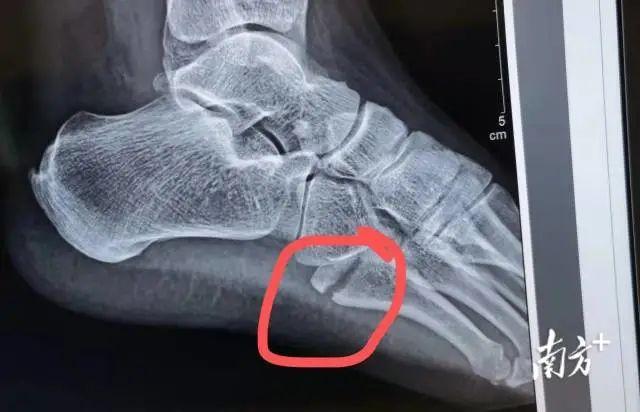

事实上,当天从采样点撤下来

黄恒一身冷汗

回到医院,拍片一看

左足第5趾骨基底部骨折

如果不马上治疗

会导致脚部肿胀加重、骨折移位

将来可能影响肢体的功能

3月16日中午

黄恒在手术中打入了2枚钢钉